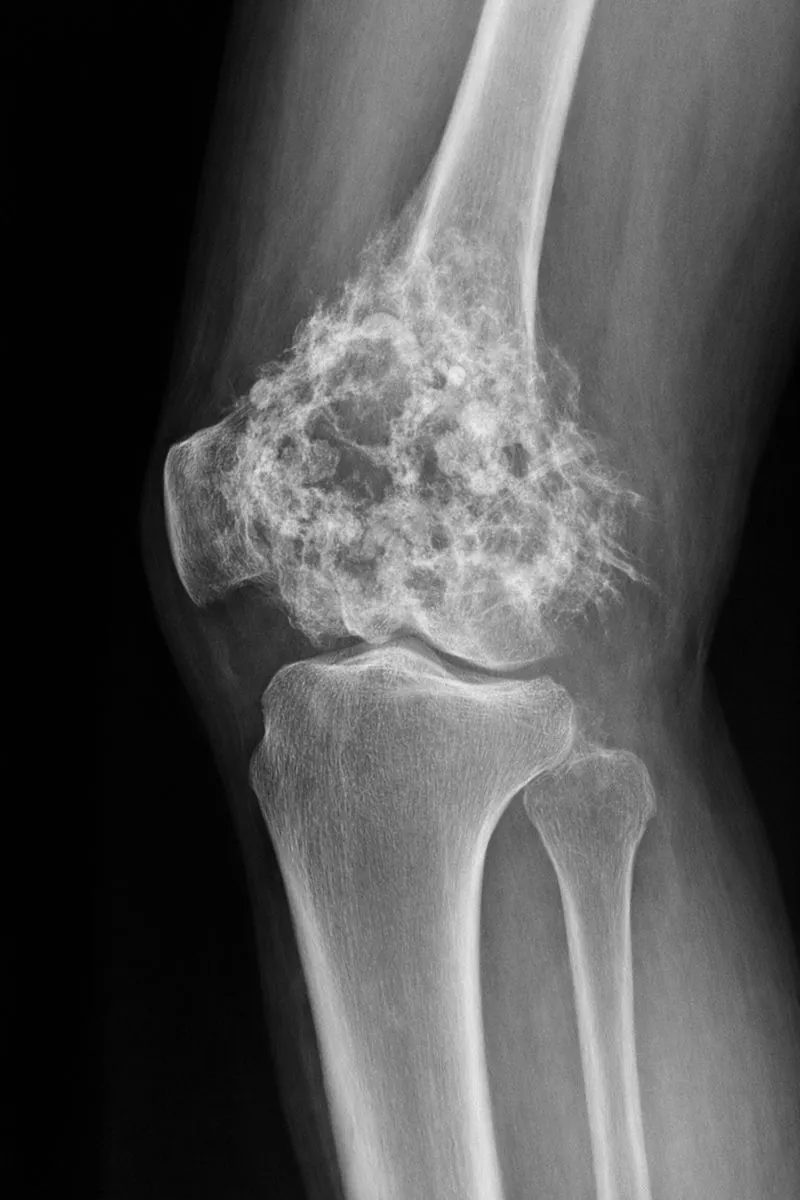

5) Óriássejtes tumor (GCTB – Giant Cell Tumor of Bone) – jóindulatú, de „agresszív”

Az óriássejtes csonttumor hivatalosan többnyire jóindulatú, de helyileg agresszíven viselkedhet (csontpusztítás, kiújulás).

Jellemző:

- gyakran térd körül (distalis femur, proximális tibia)

- fájdalom, duzzanat, terhelési panasz

- kezelése gyakran műtéti (kürett + adjuváns eljárások), bizonyos esetekben gyógyszeres terápia is szóba jöhet szakorvosi centrumokban